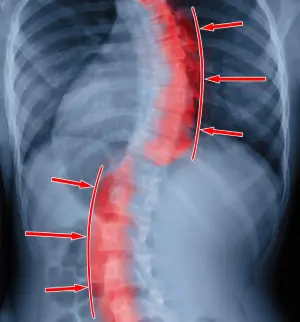

Spine Problem

Are You Experiencing Back or Neck Pain?

Chronic back pain affecting daily life

Numbness or tingling in limbs

Difficulty walking or standing

Herniated disc, spinal stenosis, deformity